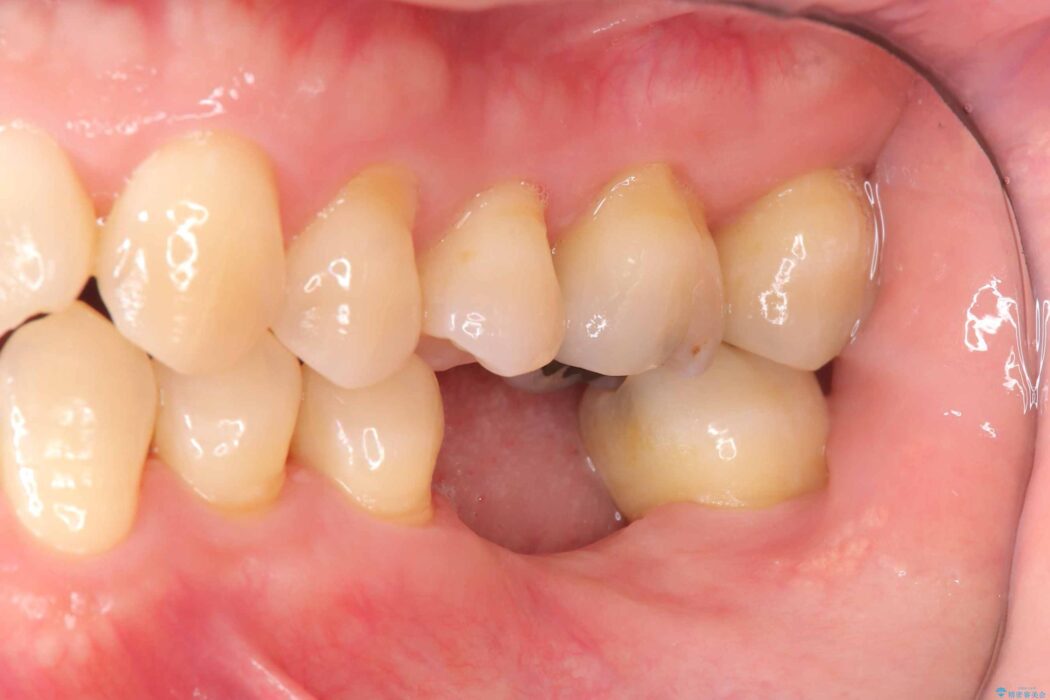

治療後について

インプラント治療は手術が一度で完了し、術後の痛みもほとんどありませんでした。

機能面・審美面ともに大きく改善され、大変ご満足いただけました。